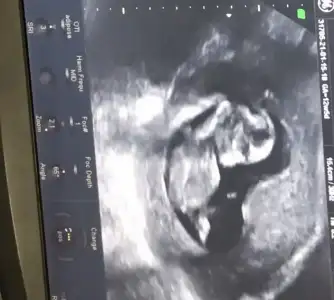

Erkek görünüyorMerhaba 11+6 tahmin edermisiniz

Net değil nubu emin olamadim başka USG varsa paylaşın sanki kız ama emin değilimMerhaba 12 haftalık tahmin edebilir misiniz![]()